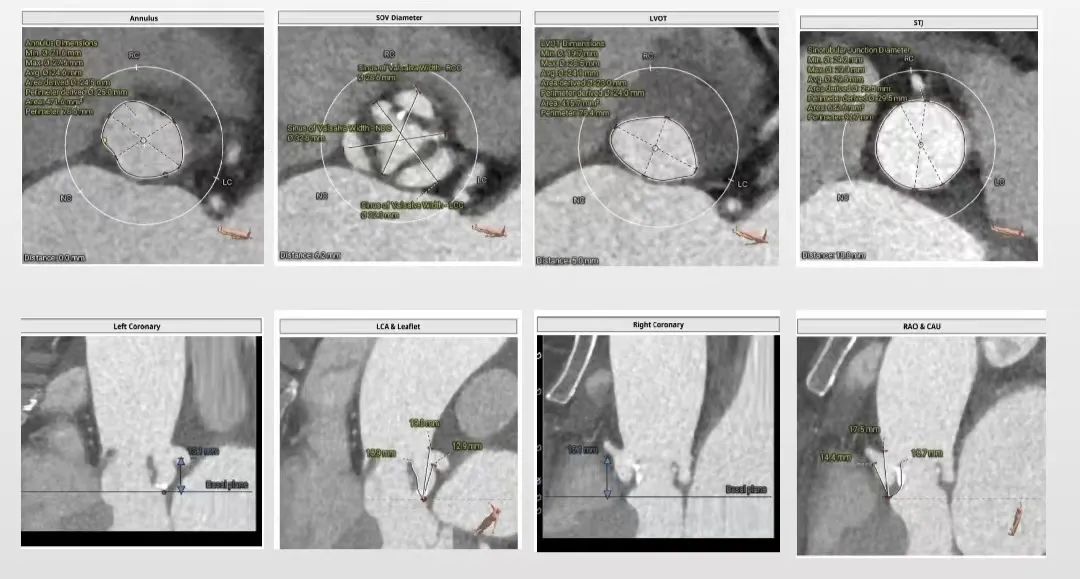

1. 主动脉瓣瓣环周长78.6mm,平均周长径25mm;

2. 功能型型二叶式主动脉瓣,R-L纤维融合嵴,瓣叶增厚,左室流出道开口呈直筒状;

3. 左右冠开口高度可,瓣叶冗长,左、右冠瓣叶长度>瓣叶附着缘到冠脉开口距离;

4. 瓦式窦内径、窦管交界内径可,升主动脉轻微扩张;

主动脉根部评估:

瓣环上解剖结构评估: